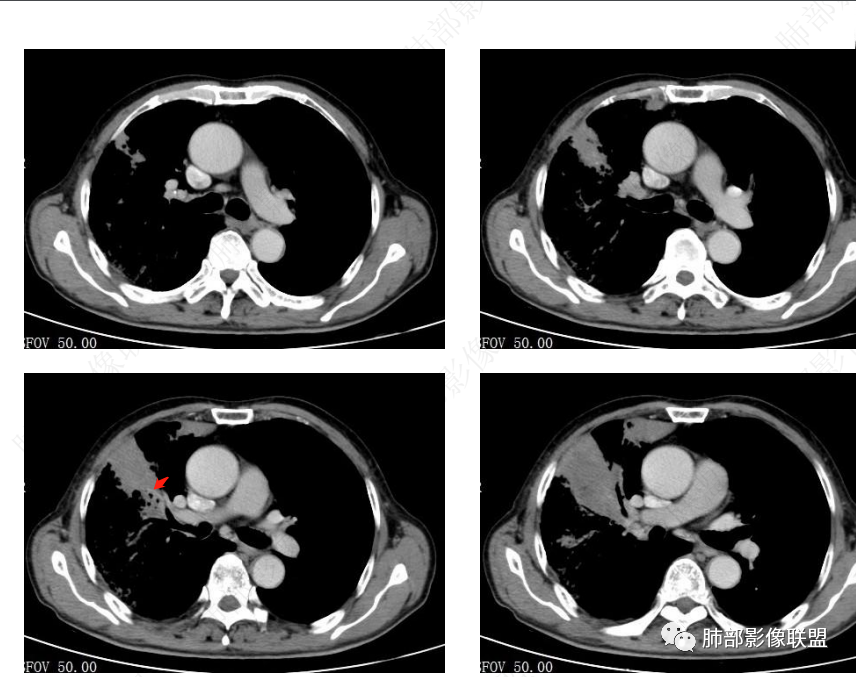

右肺上叶实变,宽基底与胸膜相连,邻近胸膜积液,上叶支气管阻塞,不均匀强化,血管显示可,局部坏死环形强化,可见气泡,考虑慢性炎症伴脓肿,放线菌?鉴别腺癌

右肺上叶尖段大片状实变,近肺门侧支气管闭塞,并可见病灶内部有片状液化坏死区,有空泡气体,病灶紧贴胸膜,胸膜反应性增厚,伴有少见积液,增强扫描内部不均匀强化,血管走形正常。影像符合慢性化脓性感染。

右肺上叶大片实变影,内密度不均匀,可见坏死环形强化,支气管被粘液栓阻塞,首先考虑感染性病变,奴卡?放线菌感染?

右肺上叶大片实变,密度不均,近端环形强化并见空泡,病灶与胸膜广基相连,之间并可见积液,考虑放线菌,鉴别腺癌

晨读:右肺上叶实变,密度欠均匀,不均匀强化,内血管走形可,近端环形强化并见空泡,考虑放线菌可能,鉴别腺癌

右主支气管周围多发淋巴结肿大融合(提示右主支气管有外受压变窄),右肺上叶尖前不张,内见支气管粘液栓和坏死及环形强化特点,邻近胸膜增厚及右肺上叶后段支气管扭曲及狭窄后扩张,周边索条纤维化,综合TB表现,超声支气管镜检查。

图不太清,好像支气管粘液栓在肺门区突然截断

右肺门结节,显著强化,内可见坏死及悬浮气泡,远端阻塞性肺不张,心脏纵隔右移,结节及不张内血管影走行自然,并可见粘液拴,隆突下淋巴结肿大,慢性病程,病变跨叶,首选感染性病变放线菌感染,其次鉴别腺癌

有脓腔,内壁光滑、强化环——支持感染

远端是不张合并感染

关键点在肺门,我需要看清楚肺门的表现,远端的是继发的